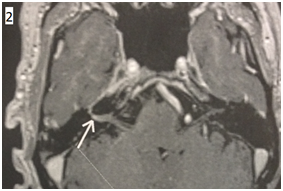

The cerebral MRI showed a Gadolinium enhancement of the right facial nerve above his emergence from the protuberance (Figure 2).

• Figure 2 Cerebral MRI showing T1 Gadolinium enhancing of the right facial nerve ( white arrow) on Coronal (1) and axial (2) sequences.